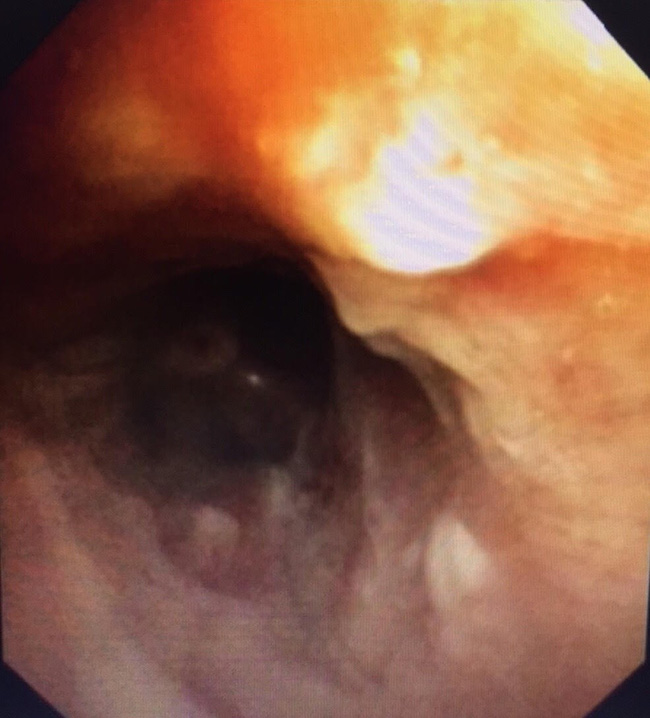

Theo đó, bệnh nhân nhập viện vào lúc 11 giờ 45 phút ngày 23/9, trong tình trạng ho nhiều, khó thở. Các bác sĩ của Bệnh viện Phổi Trung ương đã khẩn trương tiến hành hội chẩn và quyết định nội soi phế quản cấp cứu để gắp dị vật khí quản, giải phóng tắc nghẽn đường thở, nhằm cứu sống người bệnh.

Ngay sau đó, bệnh nhân đã nhanh chóng được gắp thành công dị vật ra khỏi phế quản, giải phóng đường thở. Dị vật này là 1 cầu răng sứ 4 răng hàm dài 3,5cm đã bị rơi vào khí phế quản trong quá trình lắp răng giả cho người bệnh.

Dị vật này là 1 cầu răng sứ 4 răng hàm dài 3,5cm đã bị rơi vào khí phế quản của bệnh nhân.

Theo bác sĩ Minh, đây là một kỹ thuật y khoa khó vì dị vật quá to và trơn nhẵn do răng giả làm bằng sứ.